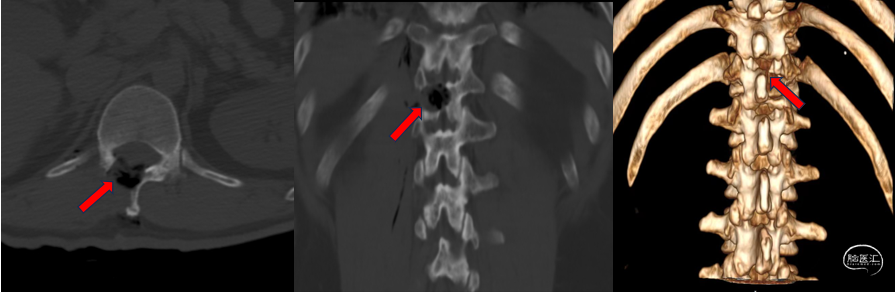

术后检查(胸椎CT重建):

![]()